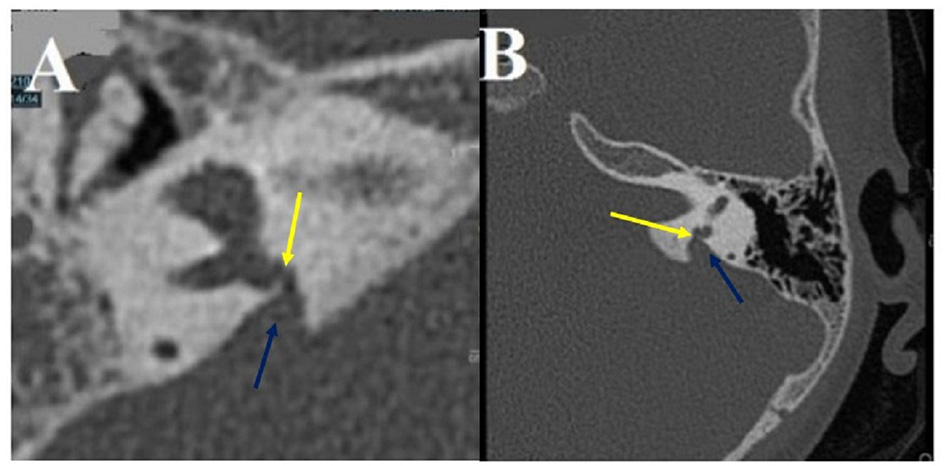

Type IIb

Concern OCD involving the internal jugular vein (IJV) and various vestibular structures.

A dehiscence involving the vestibular aqueductus (VA) in contact with the IJV (Figures 2A,B) was found in 20 ears (14 right-sided, 6 left-sided), in 19 patients (6M, 13F), aged 11–72. The presentation was bilateral in one patient (1F). A dehiscence between IJV and PSC was found in 5 temporal bones (3 right-sided, 2 left-sided) in 4 patients (4F) aged 12–50. A dehiscence concerning the IJV and the cochlear aqueductus (CA) was found in 3 ears (left-sided) in 2 patients, age varying from 12 to 53 (1M, 1F).

In this subtype, the second most prevalent in our series as it was diagnosed in 19 from 97 patients, vertigo and/or pulsatile tinnitus induced by exertion were also constantly reported. Positional vertigo was also a commonly reported symptom with no evidence for a true benign positional paroxysmal vertigo (BPPV).

Intralabyrinthine TMWA-like. (A,B) Vestibulo-vestibular dehiscence: between the vestibular aqueduct widened to 3 mm (blue arrow) and the right posterior SC (yellow arrow) at the level of the common crus (B).

Figure 5

Multiple localization OCD (case report 1): high-riding left IJV at the origin of two type II of OCD. (A) Procidence of the IJV in the IAC (White arrow), a thin bone lamina is still remaining, (B) Dehiscence between IJV interface and VA. (C) Dehiscence between IJV interface and CA. IJV, internal jugular vein; IAC, internal auditory canal; VA, vestibular aqueduct; CA, cochlear aqueduct.